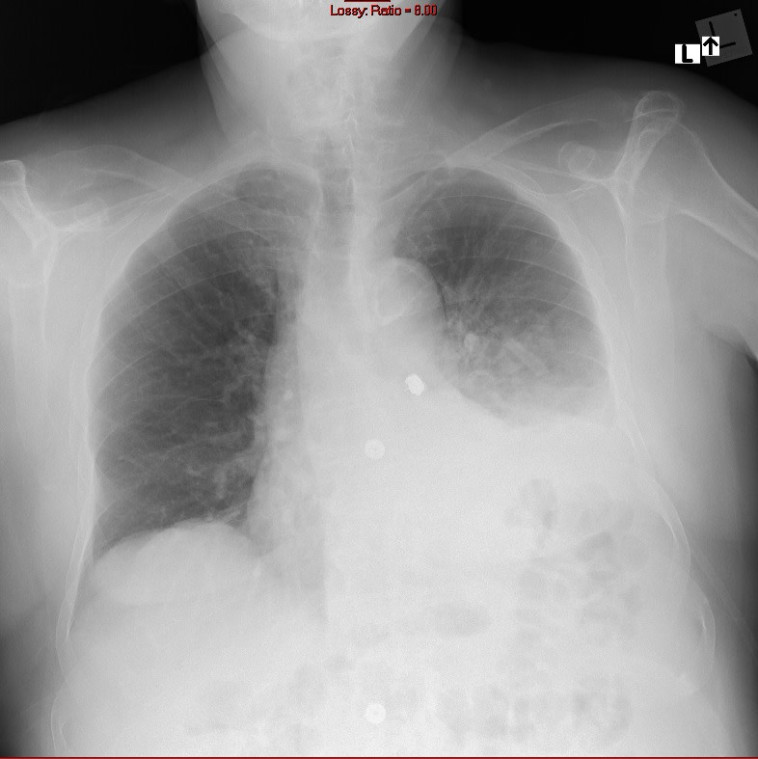

צילום החזה בו נראית השן בתוך הריאות של מ'

צילום החזה בו נראית השן בתוך הריאות של מ' | צילום: דוברות מרכז רפואי ''מאיר'' מקבוצת ''כללית''